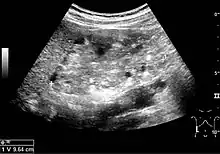

Three methods of scanning can detect Angiomyolipomas: ultrasound, computed tomography (CT), and magnetic resonance imaging (MRI).[5] Ultrasound is standard and is particularly sensitive to the fat in Angiomyolipomas, but less so to the solid components. However, accurate measurements are hard to make with ultrasound, particularly if the Angiomyolipoma is near the surface of the kidney (grade III).[4] CT is very detailed and fast, and allows accurate measurement. However, it exposes the patient to radiation and the dangers that a contrast dye used to aid the scanning may itself harm the kidneys. MRI is safer than CT, but many patients (particularly those with the learning difficulties or behavioural problems found in tuberous sclerosis) require sedation or general anaesthesia, and the scan cannot be performed quickly.[3] Some other kidney tumours contain fat, so the presence of fat is not diagnostic. Distinguishing a fat-poor angiomyolipoma from a renal cell carcinoma (RCC) can be difficult.[6] Both minimal fat AMLs and 80% of the clear-cell type of RCCs display signal drop on an out-of-phase MRI sequence compared to in-phase.[7] Thus, a lesion growing at greater than 5 mm per year may warrant a biopsy for diagnosis.[3]